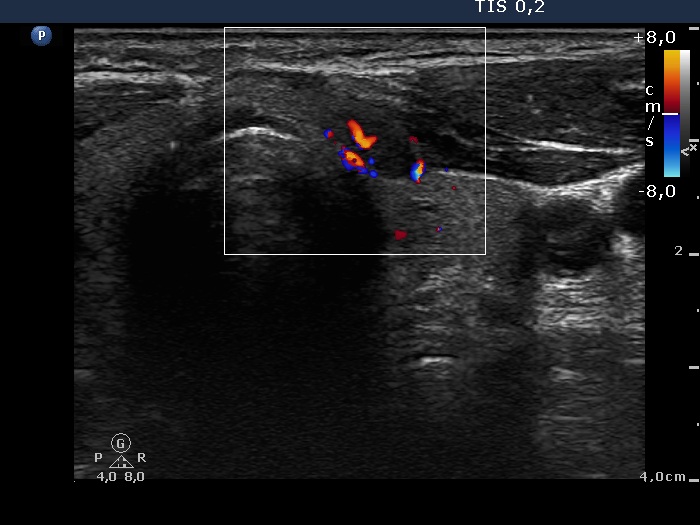

Ultrasonography. There was a moderately hypoechogenic nodule with increased intranodular blood flow in the right lobe, while a smaller hypoechogenic lesion in the medial part of the left lobe. The latter also displayed intranodular vascular pattern. Corresponding to the lump in the left submandibular area, there were enlarged lymph nodes with an irregular vascular pattern.